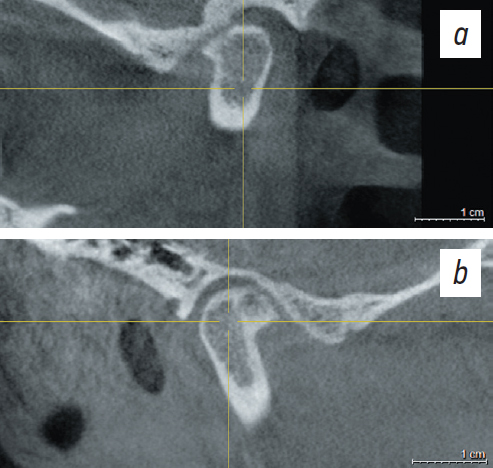

A follow-up TMJ CT was performed after wearing occlusal splints (Fig. 9).

Fig. 9. Section of a computed tomogram of the right (a) and left (b) temporomandibular joints after using a mouth guard.

Рис. 9. Срез компьютерной томограммы правого (a) и левого височно-нижнечелюстного сустава (b) после использования каппы.